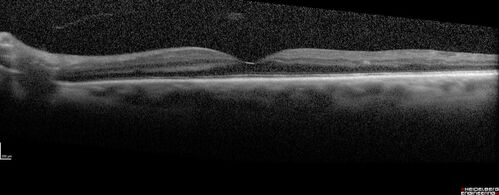

Prethreshold PDR right eye - mild NVD

Pre-Threhold PDR right eye NVD